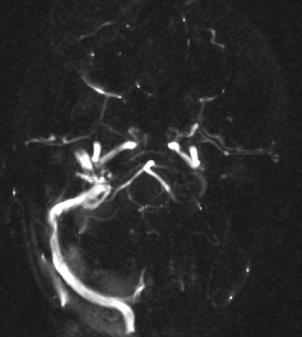

MR angiography (MRA)

Flow void phenomenon: flowing blood, within the cross sectioned vessels in the examination slice, will be signal free. This happens because blood that gets excited by the RF pulses will move out of the imaging slice at signal registration, and it will be replaced by non-excited blood. Therefore, blood vessels in Spin Echo sequences will be highly distinguishable due to this signal void.

Angiographic techniques:

Time of Flight (TOF) is the time it takes for flowing blood to pass through a slice. With the use of very short repetition time, blood vessels will show very high signal intensity (it needs a fast acquisition like Gradient Echo sequence - GRE).

Phase contrast technique (PC) relies on the fact that the flowing spins (the moving protons) lose their phase (desynchronize) faster than stationary tissues. Its advantage is that it can measure flow velocity as well, and it is independent from the direction of the flow.